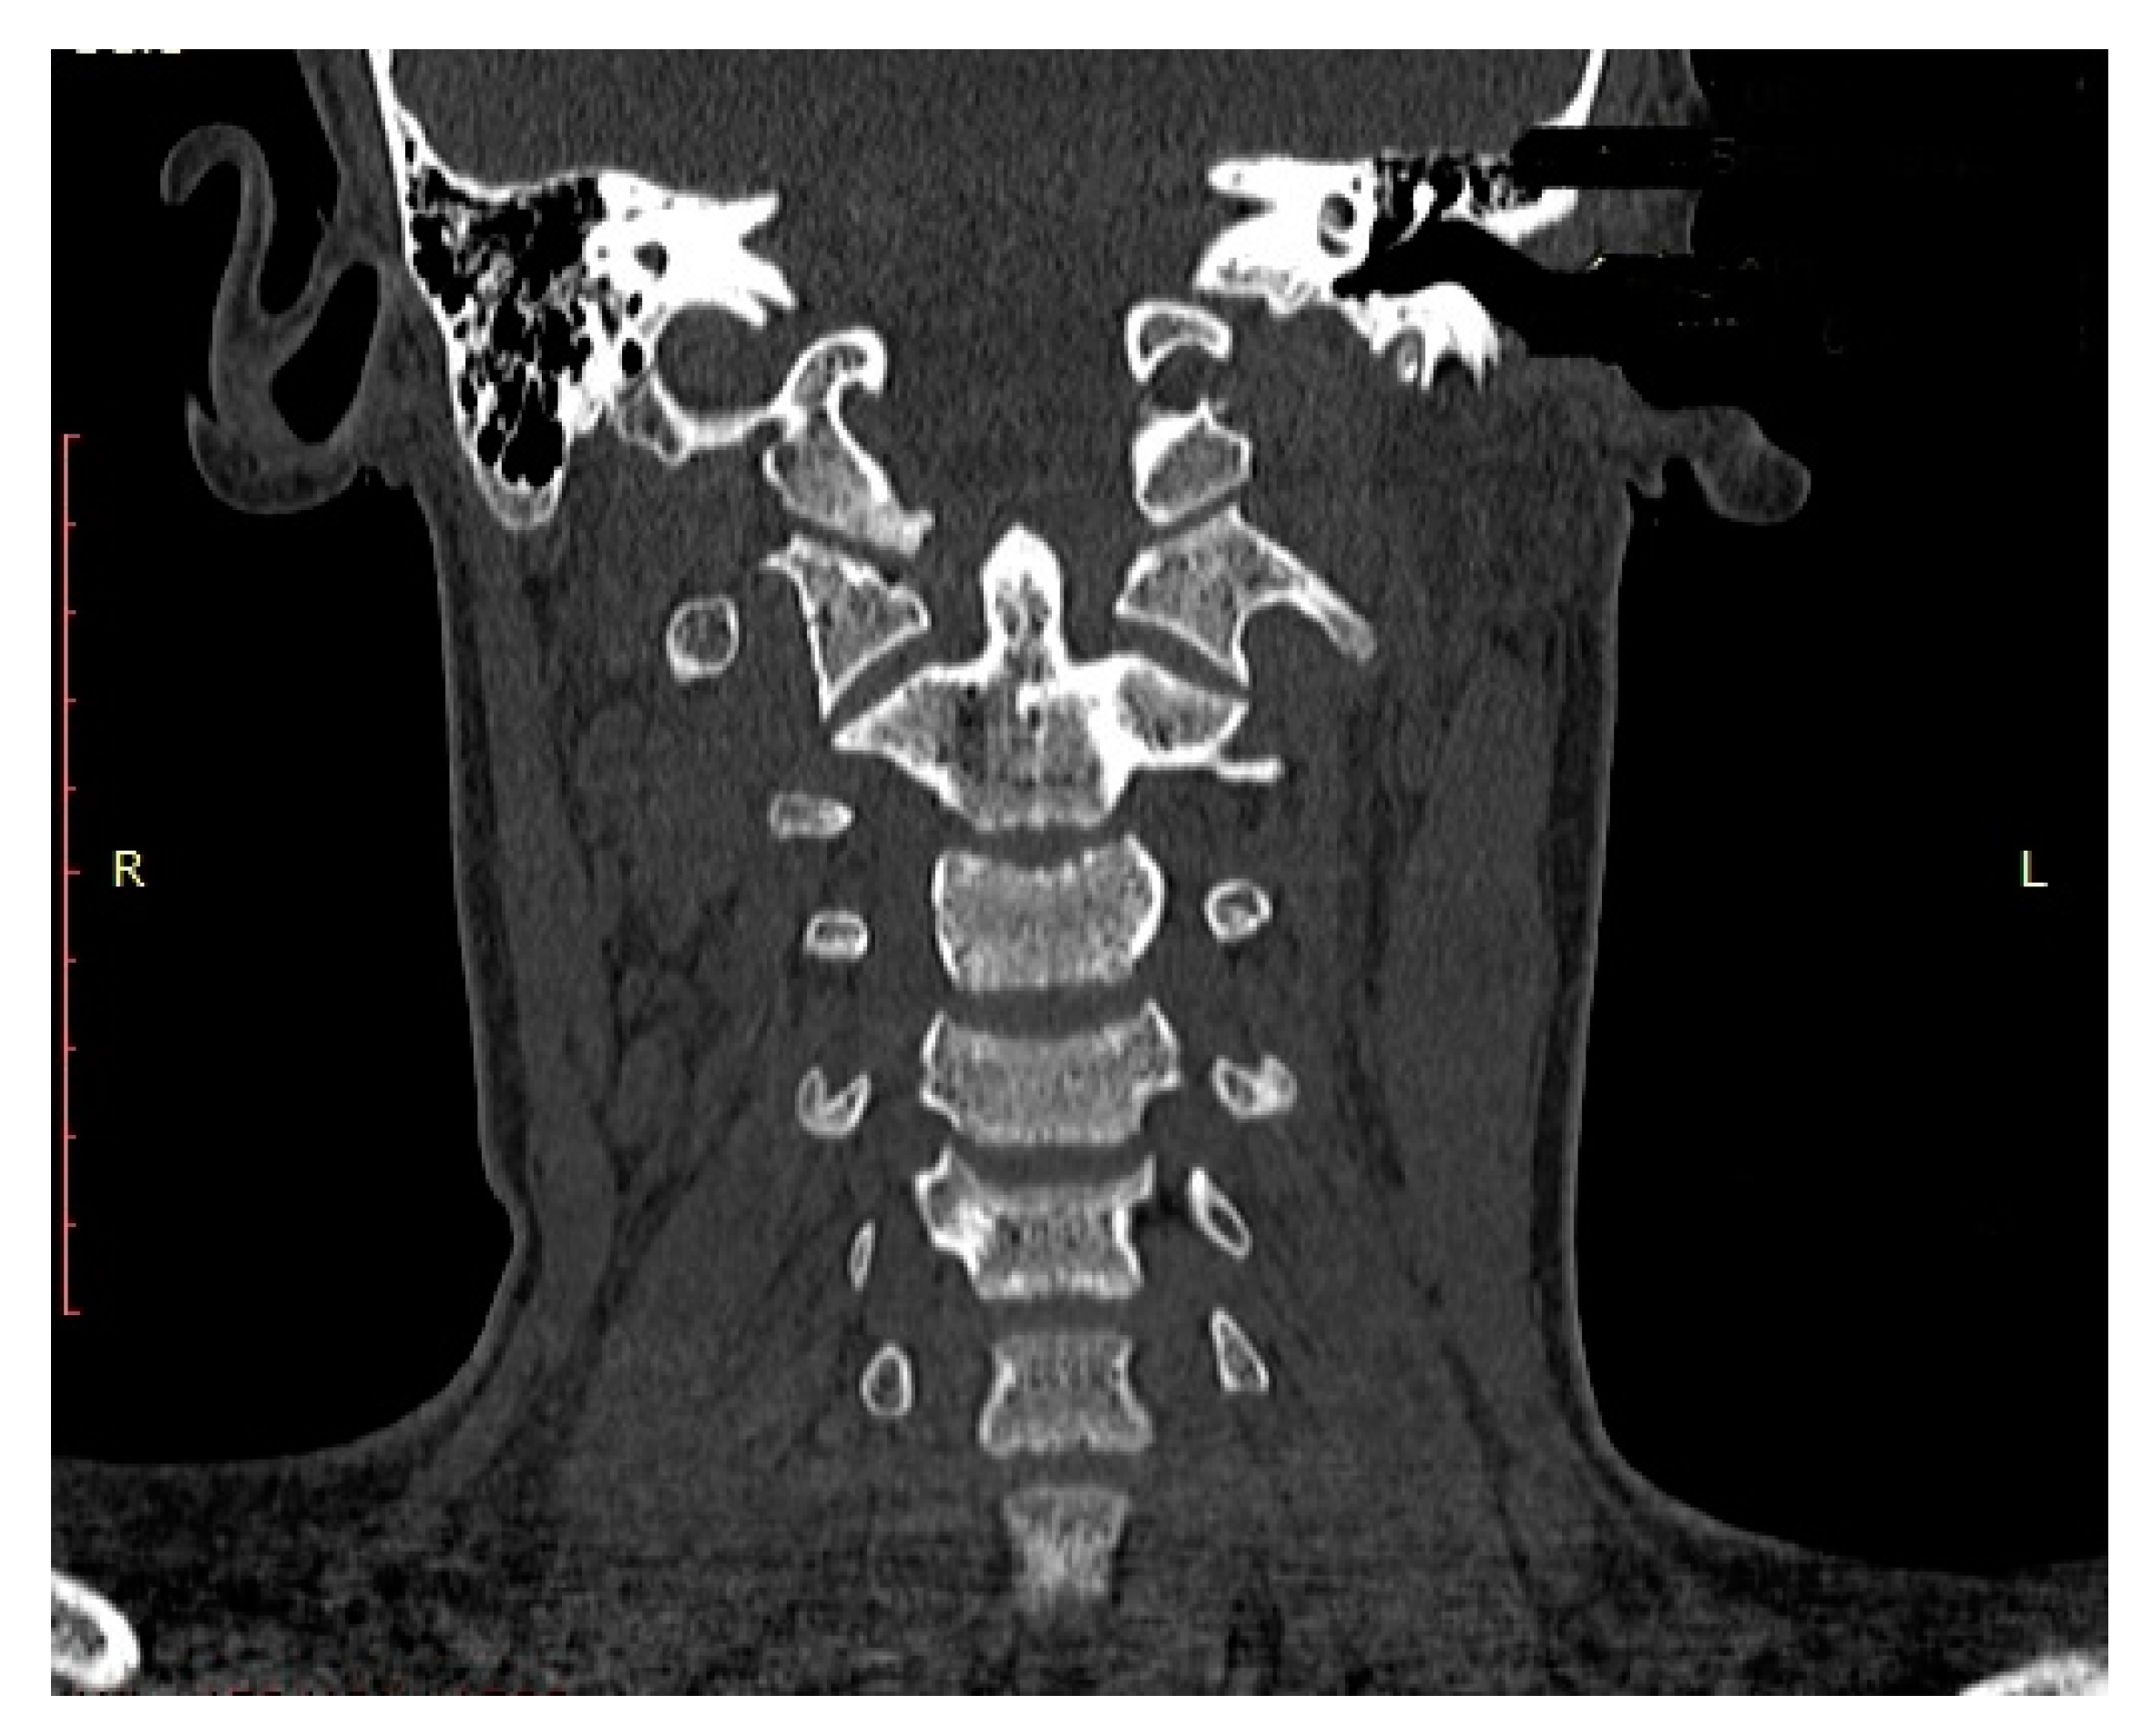

- We recommend CT and MRI of the CCJ to diagnose OCF and confirm post-therapeutic fracture consolidation in pediatric patients.

| Name (Initials) | Sex (Male/ Female) | Age (Years) | Anderson Montesano Classification | Tuli Classification | Cause of Injury | Accompanying Injuries | Immobilization Method |

|---|---|---|---|---|---|---|---|

| P.P. | M | 15.2 | III (unstable) | IIB | Road traffic accident (car passenger) | Fracture frontal bone, fracture frontal sinus, contusion of frontal lobe | Halo-vest immobilization: 12.5 weeks |

| K.D. | F | 15 | III (unstable) | IIB | Pedestrian hit by car | Lung contusion, brain concussion, multiple abrasions | Halo-vest immobilization: 13 weeks |

| R.M. | F | 18 | I (unstable) | IIB | Road traffic accident (car passenger) | Pneumothorax, neurogenic vocal cord injury, post-traumatic aphasia | Halo-vest immobilization: 14 weeks |

| S.D. | M | 14.7 | III (stable) | IIA | Road traffic accident (car passenger) | Fracture of frontal bone, fracture of nasal bone, subdural hematoma | Minerva-brace immobilization |

| B.W. | F | 16 | I (stable) | IIA | Fall from a height | Fracture of frontal bone, fracture of nasal bone, subarachnoid hemorrhage, fracture of transverse process Th3-5, fracture of radius | Minerva-brace immobilization |

| M.O. | M | 16.1 | I (stable) | IIA | Bicycle incident | Fracture frontal bone, fracture maxillary sinus, fracture orbit, metacarpal fracture | Minerva-brace immobilization |